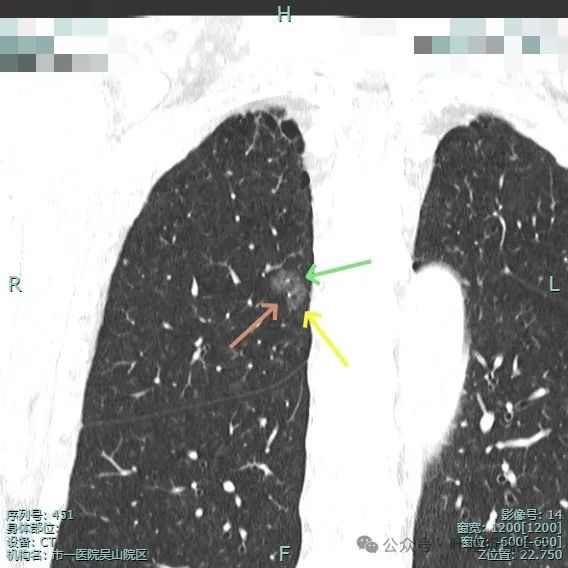

病灶磨玻璃密度,未见明显实性成分,但有血管进入。

图片

血管穿行明显,表面有毛刺征,灶内有空泡征。

分叶明显,灶内点状高密度(血管穿行)表面有细小毛刺征。

灶内密度略显不均,有空泡征,表面有毛刺征。

毛刺与血管进入,整体是纯磨,轮廓与边界清。

少许毛刺,整体轮廓清。

血管穿行并发现细小分支的样子,表面不平有细毛刺,灶内有小空泡征。

血管穿行并略有增粗,表面不平有浅分叶,整体轮廓与边界清。

血管进入并有发出分支,边缘有细毛刺,表面不光滑,整体轮廓清,瘤肺边界清楚。